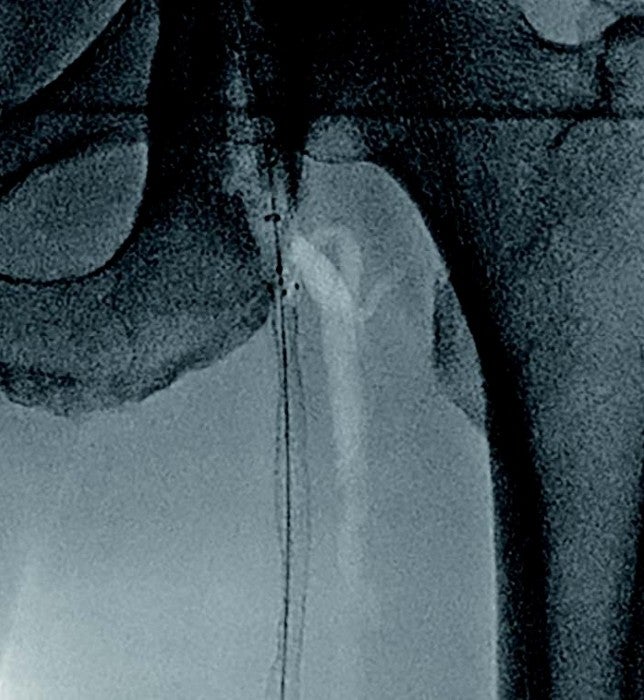

- frontal pop.A. puncture(OMOTE Hiza-pun.)を行い、0.014 inchガイドワイヤー → マイクロカテーテルを挿入。

- 閉塞近位部でCTO用0.014 inchテーパードガイドワイヤー にて6 Fr. ガイディングシース内への rendez-vousに成功。

- 6 Fr. ガイディングシース内でマイクロカテーテルへ再度rendez-vousを行いexternalization。